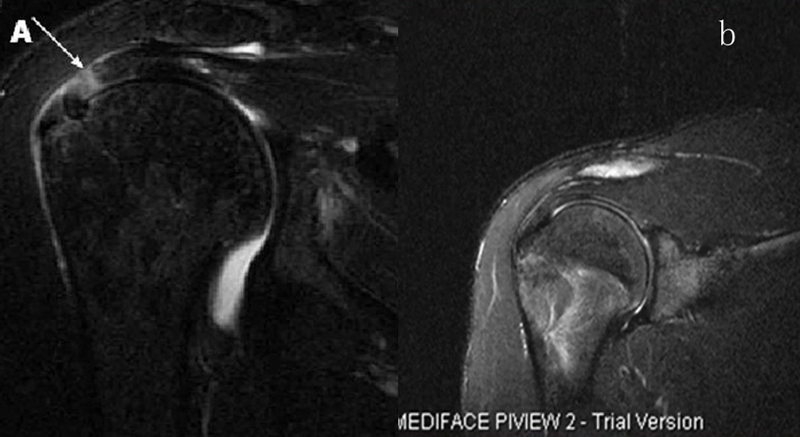

图24 a.肩袖全层撕裂;b.正常MRI

图25 巨大肩袖损伤(冈上肌)